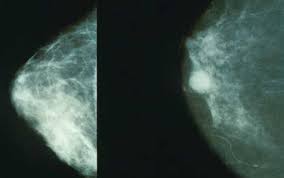

A mamografia é um exame de diagnóstico por imagem, que tem como finalidade estudar o tecido mamário. Esse tipo de exame pode detectar um nódulo, uma lesão sólida, elevada, com mais de 1 cm de diâmetro. É geralmente bem delimitada e de origem epitelial ou conjuntiva.

Pode ser pediculada ou séssil. Pode ser também benigno ou maligno. que este ainda não seja palpável.

Para tanto é utilizado um equipamento que utiliza uma fonte de raios-x, para obtenção de imagens radiográficas do tecido mamário.

Embora o auto-exame seja fundamental na saúde feminina, é aconselhável que a cada ano a mulher passe pela mamografia, que é o único exame que permite ao médico detectar alterações mínimas e revelar nódulos que não serão perceptíveis através da palpação.